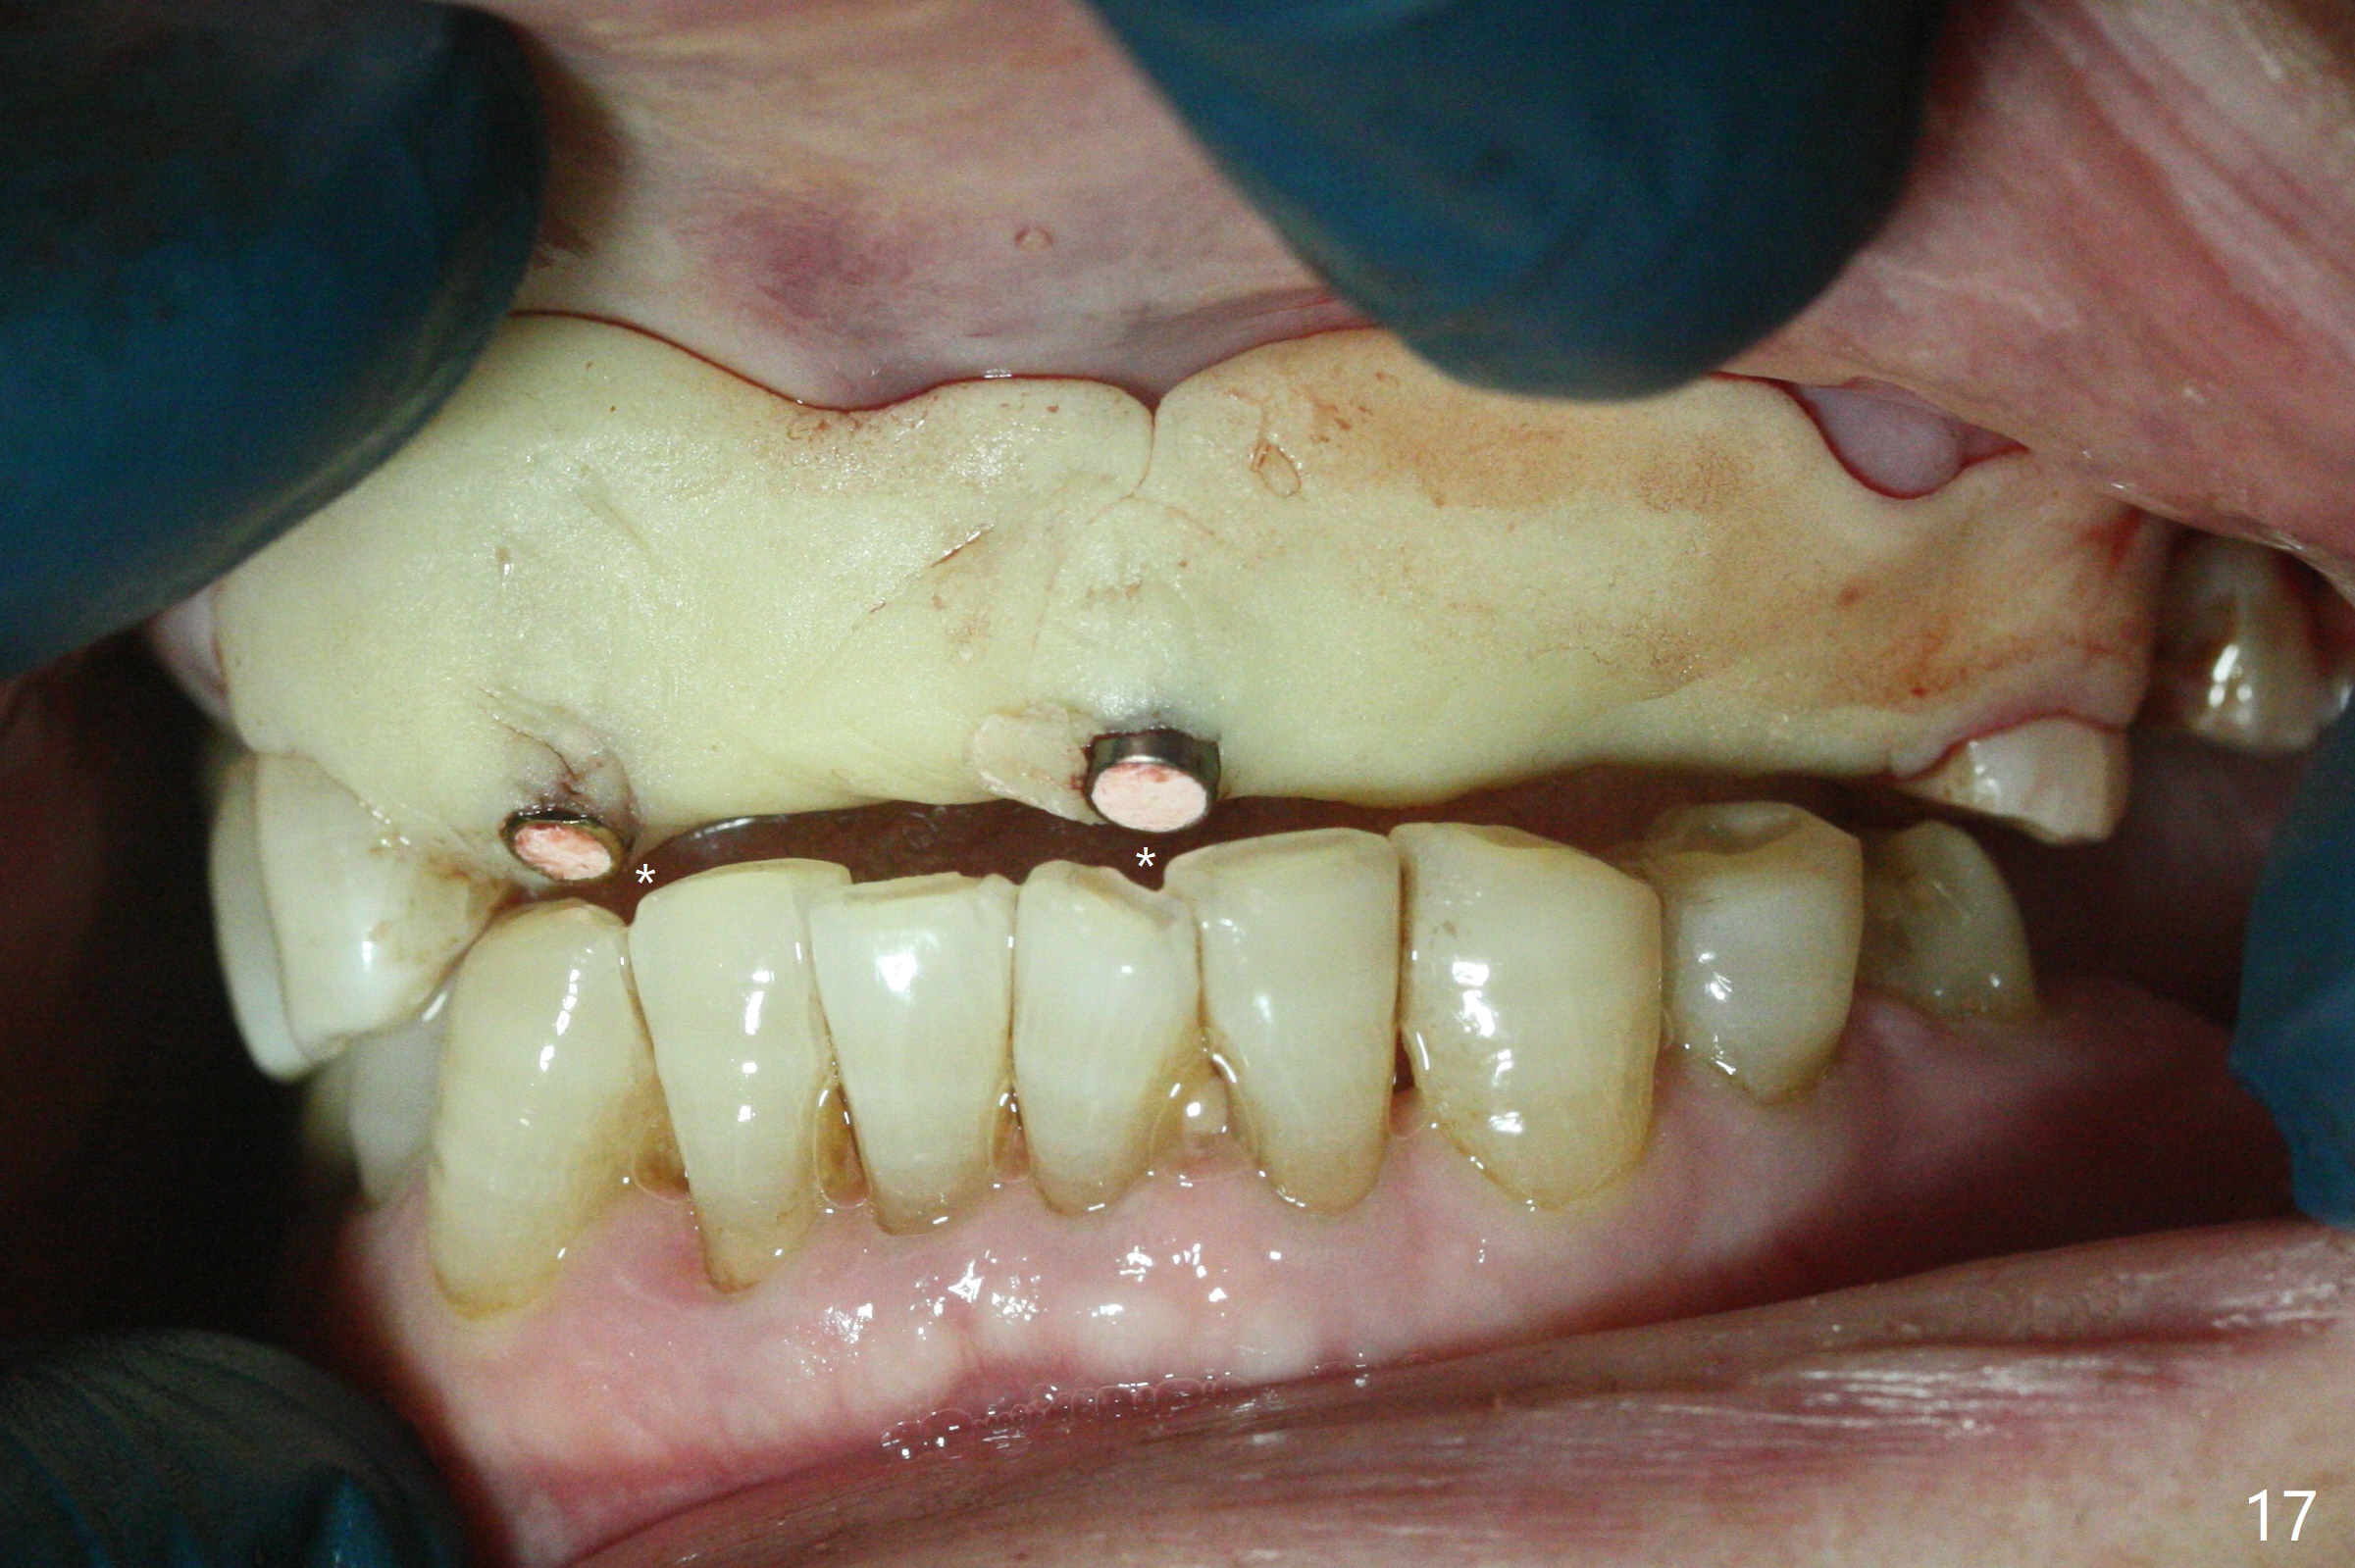

今天下午进入治疗室,粘性骨粉已制备:上清液来自红管(含促凝剂),离心3分钟(图一);再离心10分钟上清液就转变PRF,压制后,使用前剪成三块(图二:黑线),其中两块punch一个洞(图二:圆圈),插入7,9号牙基台固定;大块覆盖11/12号牙牙槽窝(图十四)。7,9,11,12号牙必须拔除(图三),然后在7,9,12种植。由于缺失左下磨牙,前牙垂直距离减少(图四)。完成9号牙位钻洞后,利用fixture mount(图五:M)植入植体,并留在原位固定导板(图六),然后7号牙种植,也留下fixture mount(图六:7,9),最后完成12号牙植入,但是后者扭力低,放置愈合螺帽(图九),而7,9号牙位放置修复基台(图七,八(使用5.5毫米profile drill后),好像基台没有完全就位。7号牙位更换基台似乎没帮助(图十),9号牙位再次放置同一个基台临床上仿佛有改变(比较图八与十二)。放置粘性骨粉后(图十一至十三),牙槽窝口覆盖PRF膜(图十四:P(A:基台)),最后使用树脂敷料固定骨粉和膜(图十五,六),基台帮助敷料固位,没有咬合干扰(图十七:*)。树脂敷料部分解决美观问题,一个月后撤除,如果植体仍有稳定性,可能制作7-10临时牙桥,可能部分维持或者恢复牙龈外形。术后一周病人主诉后面植牙和鼻底疼痛,11号牙根尖牙龈充血(图十八),轻度触痛,可能与术中尚未完全清创有关(图十九(术前CT 3D图像))。再服用Amoxicillin一周,症状好转,鼻底轻度触痛(图二十)。术后1.5月没有任何不适,撤除树脂敷料,7号牙基台(袖)显得太长,换一个短的(4.5x4(5)(图十,十一)->4x4(3)毫米)毫米),植骨好像愈合正常(图二十一:*)。7号牙换了短的基台,9号牙基台高度调整后,与对合牙有足够空间做临时牙桥,最好8,10号牙位牙龈应该凹陷(图二十二:*),有pontic外形。另外9号牙基台颊侧牙龈边缘有所修整,临时牙桥准备。先做7-10临时牙桥,理想临时牙桥pontic处树脂应该多些(图二十三:白线)压迫牙龈形成凹陷。11,12号牙牙槽窝在树脂(Bosworth)敷料下也正常愈合(图二十四)。